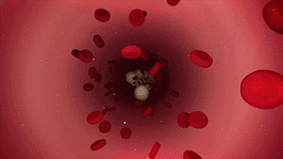

钇90是一种放射性核素,可以发射出纯β射线。钇90微球简单来说,就是含有放射性钇90物质的树脂微球,它非常小,直径仅有20-60微米,大约为人类头发丝直径的1/2。

钇90树脂微球它的治疗原理,就是通过一次微创介入手术,把数百万个钇90微球注射至滋养肝脏肿瘤的动脉血管,微球随血液进入肿瘤内部,让钇90释放的β射线近距离杀死肿瘤细胞。

由于β射线平均穿透距离仅为2.5毫米,减少了对正常肝脏组织和毗邻器官损伤,而且肝动脉的血流量高,大部分放射性物质均由肝肿瘤吸收,正常细胞接收极少,这种治疗方式更直接、更精准,而且最大程度避免了传统化疗放疗方式“杀敌一千,自损八百”带来的损伤。

钇90树脂微球被注入患者肝脏血管后,会释放高能量β放射线,可近距离对肿瘤细胞实施精准打击,且对肝脏周围的正常组织没有影响。